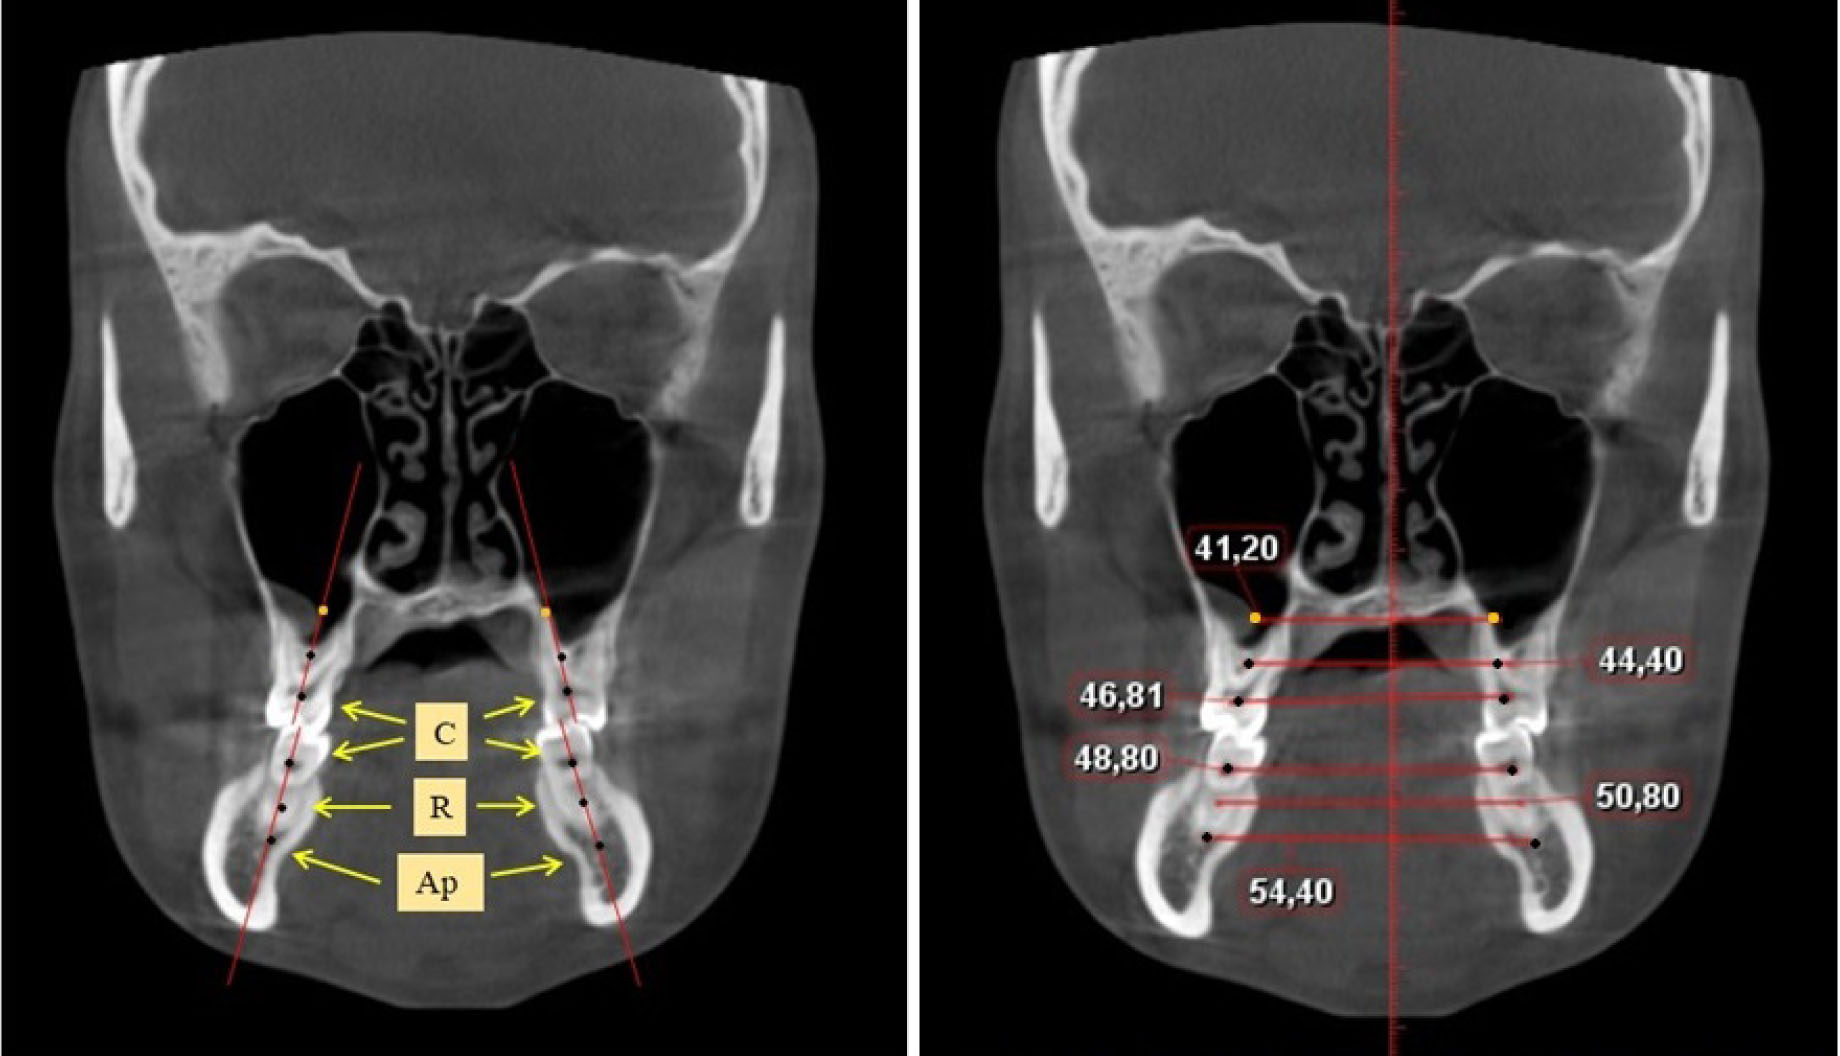

Определение ширины задних отделов зубочелюстных дуг проводили на срезах КЛКТ через дистальные поверхности вторых моляров. Проводили условные срединные вертикали вторых моляров, на которых устанавливали точки на уровне шеек зубов («С»), на уровне середины корня («R») и на уровне апикальной части корня («Ар»), как на верхней, так и нижней челюсти (рис. 2).

Рис. 2. Определение ориентиров и измерение ширины зубочелюстных дуг на КЛКТ в коронарной проекции

Рассчитывали коэффициент соотношения ширины лица с размерами альвеолярных дуг между цервикальными точками вторых верхних моляров (фациально-цервикальный коэффициент).